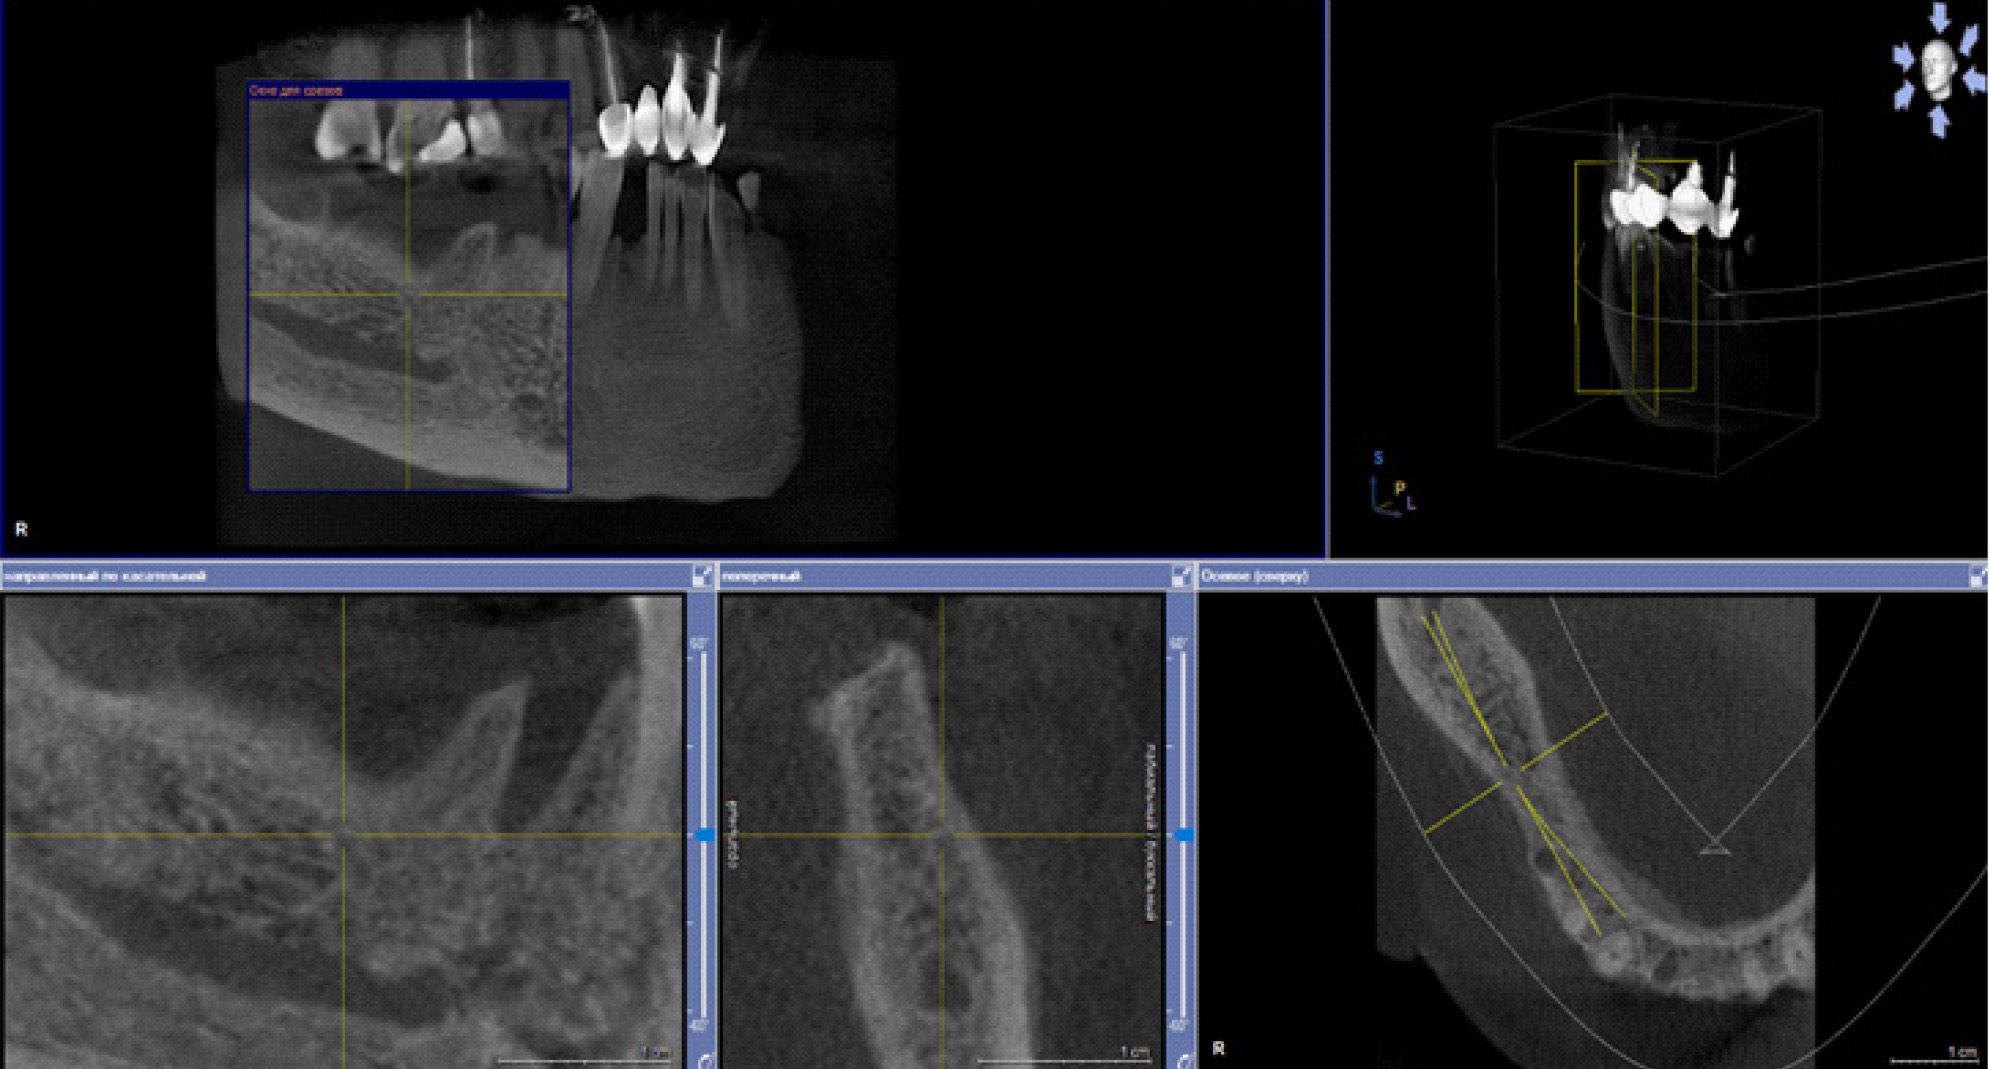

В настоящее время выделяют два основных подхода к лечению БФОНЧ, к ним относятся консервативный и хирургический подход. Выбор тактики лечения пациента зависит от стадии заболевания. Консервативное лечение предусматривает назначение пациентам курсовой антибактериальной, симптоматической терапии препаратов для улучшения микроциркуляции, ежедневной обработки очагов поражения костной ткани растворами антисептиков, частичная некроэктомия, удаление подвижных секвестров, а также тщательное соблюдение гигиены полости рта (рис. 4).

Рис. 4. Компьютерно-томографическое исследование на этапе лечения остеонекроза нижней челюсти справа у пациентки Б. в 2023 г.

За период лечения пациентки Б. было выполнено хирургическое лечение в следующем объеме: кюретаж лунок удаленных зубов, частичная секвестрэктомия, резекция альвеолярной части нижней челюсти справа, вскрытие и дренирование гнойных очагов в стадии обострения патологического процесса. Отмечалось улучшение клинической и рентгенологической картины в полости рта (рис. 5, 6).